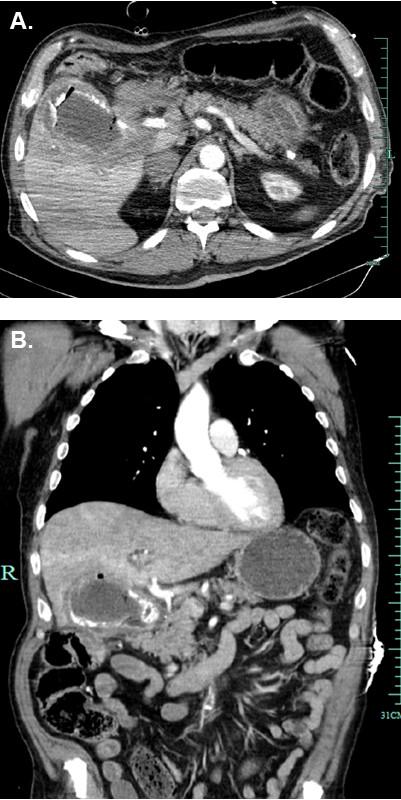

We present the case of a 70-year-old male, who suffered from a 3 x 4 cm duodenal defect caused by duodenal pressure necrosis due to a 12.5 x 5.5 x 5 cm gallstone. Additionally, this stone caused intestinal obstruction (Bouveret's syndrome) and bleeding with signs of shock. Besides the gallstone extraction, the common bile duct was drained by a T-tube and the duodenal defect closure was performed by a gastroduodeno-plasty and Bilroth II gastroenterostomy. The postoperative phase was uneventful. The reconstructed duodenum was endoscopically accessible and showed no pathological findings on follow-up.

我们报告一例70岁男性病例,其因一枚12.5×5.5×5厘米的胆结石导致十二指肠压迫性坏死,出现了一个3×4厘米的十二指肠缺损。此外,该结石还引发了肠梗阻(布-加综合征)并伴有休克迹象的出血。除了取出胆结石外,通过T形管对胆总管进行引流,并采用胃十二指肠成形术和毕罗Ⅱ式胃肠吻合术对十二指肠缺损进行修复。术后过程顺利。重建后的十二指肠在内镜检查时可及,随访未发现病理改变。